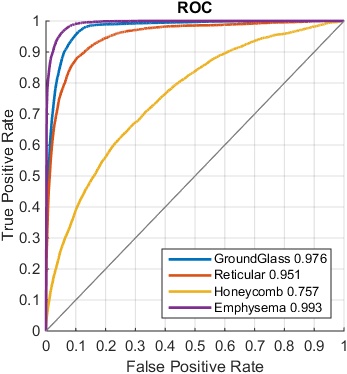

When constructing the FV-encoded features, , the local convolutional image descriptors are pooled into Gaussian components, producing a dimensionality as high as 16K [21]. We further reduce the FV features to dimensions using PCA. The performance is empirically found to be insensitive to the number of Gaussian kernels and the dimensions after PCA. We compare the ILD classification performance with FV encoding, on the features pooled from different CNN layers, using area-under-the-curve (AUC) values (in Table 5) and F-scores (in Table 6), respectively.

| AUC | |||||||

|---|---|---|---|---|---|---|---|

| Disease | conv1 | conv2 | conv3 | conv4 | conv5 | fc6 | CNN |

| Ground Glass | 0.979 | 0.978 | 0.984 | 0.985 | 0.984 | 0.970 | 0.990 |

| Reticular | 0.951 | 0.953 | 0.955 | 0.957 | 0.950 | 0.900 | 0.964 |

| Honeycomb | 0.765 | 0.770 | 0.780 | 0.744 | 0.753 | 0.743 | 0.809 |

| Emphysema | 0.985 | 0.990 | 0.987 | 0.989 | 0.988 | 0.985 | 0.995 |

When evaluated using a smaller ILD dataset, the same as the one used in [11, 1] of 18k CT slices, FV order-less encoding is effective as demonstrated in Table 7. The unordered pooling operating on the first CNN convolutional layer conv1 produces the overall best quantitative results, especially for honeycomb. Despite residing in the first layer, the filters and activations on conv1 are still the integrated parts of a deep network since they are learned through back-propagation from deeper layers. From Table 7, FV encoding with deeply-learned conv1 filter activations produces the best ILD classification against FV encoding on other layers and without FV. Nevertheless, for the much larger dataset of 240k CT images under 5-fold CV, the computational complexity of FV encoding becomes the performance bottleneck. It could take an undesirably long time and huge memory requirement to calculate the FV Gaussian components and perform the feature encoding. In our experiments, we randomly select a smaller subset of deep activation features (1/3) to calculate FV encoding, which may limit the FV encoding performance. In this setting of sufficiently large amount of data, CNN models without FV encoding perform better.

| AUC | |||||||

|---|---|---|---|---|---|---|---|

| Disease | conv1 | conv2 | conv3 | conv4 | conv5 | fc6 | CNN |

| Ground Glass | 0.984 | 0.955 | 0.953 | 0.948 | 0.948 | 0.930 | 0.943 |

| Reticular | 0.976 | 0.958 | 0.954 | 0.951 | 0.950 | 0.939 | 0.917 |

| Honeycomb | 0.898 | 0.826 | 0.828 | 0.823 | 0.806 | 0.773 | 0.698 |

| Emphysema | 0.988 | 0.975 | 0.967 | 0.966 | 0.967 | 0.985 | 0.988 |